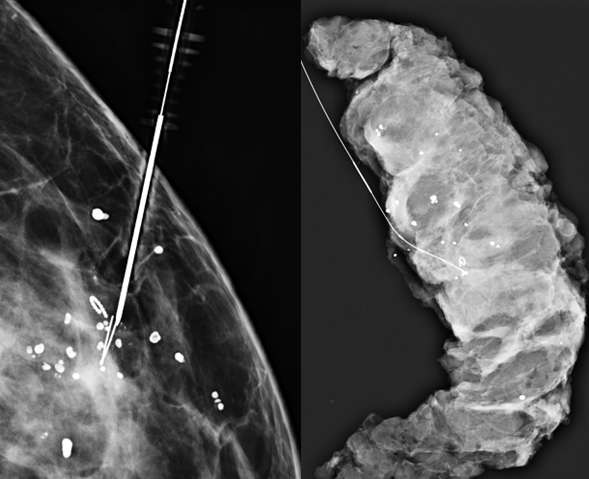

Technologist takes 2D or 3D mammogram with wire(s) in place (Figure 4).

Procedure Mammographically Guided Wire Localizations Figure 4

Figure 4: Left: Final image with wire in place (inside the hollow needle). The end of the wire hook is appropriately located just beyond the residual microcalcifications. Right: Surgical specimen radiograph confirms removal of microclip and microcalcifications along with the wire.